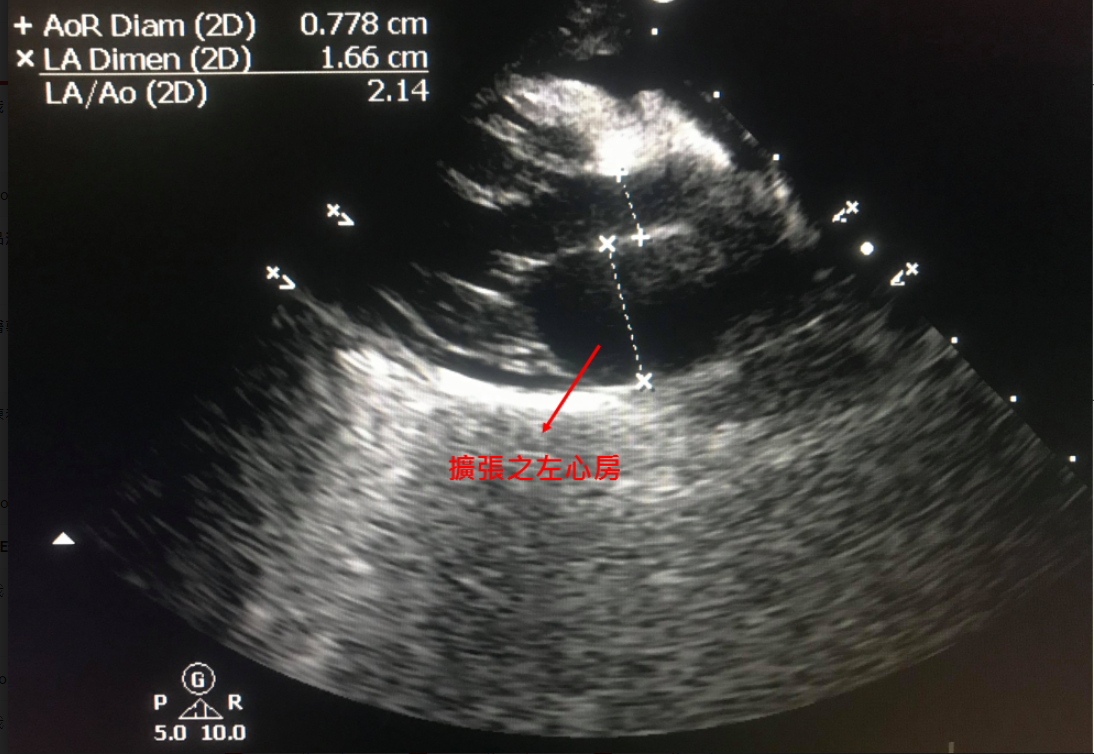

心臟快速掃描結果

嚴重的左心房擴張

以下病例為10歲已絕育米克斯公貓,主人希望安排麻醉洗牙,術前健康檢查中發現貓咪已有嚴重心臟病,但主人平常並沒有發現任何異常。

及時發現心臟病,重新評估手術的必要性,調整麻醉及術後照護計畫可以避免事後的遺憾!